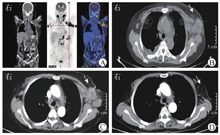

患者女,59岁,因"发热伴淋巴结肿痛2月余"于2021年12月8日入联勤保障部队第九〇〇医院。患者于2021年9月末接种第2针新型冠状病毒疫苗后出现乏力伴低热,未诊治。10月5日开始出现畏寒、寒战、发热,最高体温达39.0 ℃,伴双颈部及腋下淋巴结肿大,触之疼痛明显。就诊于当地县医院,予地塞米松、克林霉素治疗,无改善。10月7日就诊于当地市医院血液科,实验室检查:白细胞计数为48.52×109/L,中性粒细胞比例为0.887,血小板计数为300×109/L,血红蛋白为87 g/L;CRP为222.66 mg/L;ESR为109.0 mm/1 h;抗核抗体为1∶100,抗SSA抗体弱阳性,抗SSB抗体阳性;甲状腺功能3项(游离三碘甲状腺原氨酸、游离四碘甲状腺原氨酸、促甲状腺激素)、肿瘤标志物(AFP、癌胚抗原、糖类抗原125、糖类抗原19-9)、呼吸道病原体(肺炎衣原体、肺炎支原体、呼吸道合胞病毒、腺病毒、柯萨奇病毒)IgG均正常;T-SPOT.TB不确定,PPD阴性。CT检查示双肺少量炎症,纵隔、腹腔、腹膜后、左侧锁骨上区及双侧腋窝多发大小不等淋巴结,双侧胸腔少量积液。右侧腋窝淋巴结活检病理示:淋巴细胞增生,局灶坏死,考虑组织细胞性坏死性淋巴结炎(histiocytic necrotizirg lymphadentis, HNL);骨髓穿刺提示粒细胞增生明显,粒细胞核左移,红细胞、血小板正常。予依替米星、左氧氟沙星抗感染后体温恢复正常,淋巴结缩小,于10月20日出院。出院当晚再次发热,最高体温为38.2 ℃,物理降温后可恢复正常,次日午后再次升高至38.5 ℃。遂就诊于当地市医院感染科,痰培养检出念珠菌,行左侧腋窝淋巴结活检,病理示送检淋巴结构破坏,大量急慢性炎症细胞浸润及组织细胞聚集,局灶坏死及微脓肿形成,倾向HNL,免疫组织化学不考虑淋巴瘤。先后予左氧氟沙星+阿米卡星、美罗培南、利奈唑胺抗感染,氟康唑抗真菌,地塞米松抗炎等治疗,效果不佳。11月8日起予"异烟肼+利福平+吡嗪酰胺+乙胺丁醇"试验性抗结核治疗1个月。11月16日起地塞米松改甲泼尼龙口服,11月30日加用沙利度胺、羟基喹、甲氨蝶呤治疗。其间体温波动于37.4~38.1 ℃,白细胞计数波动于(27~37)×109/L。12月8日以"发热伴淋巴结肿大待查"转诊至联勤保障部队第九〇〇医院。既往30年前因淋巴结肿大就诊,口服药物(具体不详)治疗1周后自行停药;1年前因颈部淋巴结肿痛就诊于当地诊所,予抗感染、糖皮质激素处理后症状好转。个人史、婚育史、家族史无特殊。体格检查:双侧颌下、颈部及腋窝多发淋巴结肿大,质硬,部分融合,伴压痛,活动度差,表面皮肤完好无发红、破溃,双侧腹股沟淋巴结肿大,无压痛,活动尚可。双侧腋窝均见一斜行活检手术瘢痕,愈合可。实验室检查:白细胞计数为19.75×109/L,中性粒细胞比例为0.861,血红蛋白为72 g/L,血小板计数为412×109/L,ESR为57.0 mm/1 h,CRP为159.00 mg/L;生物化学检查、降钙素原、IgA、IgG、IgM、补体C3、补体C4均正常;EB病毒DNA为1.53×104 IU/mL;EB病毒抗衣壳抗原IgA抗体阳性,抗早期抗原IgA抗体阴性,抗衣壳抗原IgG抗体阳性,抗早期抗原IgG抗体阳性,抗衣壳抗原IgM抗体阴性。结合患者病史,考虑卡斯尔曼病、结核性淋巴结炎可能性大,淋巴瘤不能除外。遂予甲泼尼龙(80 mg/次,1次/d,静脉滴注)抑制炎症反应,左氧氟沙星(0.5 g/次,1次/d,静脉滴注)预防性抗感染,保胃,补钙等治疗。进一步完善相关检查:结核抗体阳性,PPD阳性,γ干扰素释放试验(interferon-γ release assay, IGRA)不确定;12月14日PET-CT检查示,全身多部位、多发肿大淋巴结,呈高代谢,考虑淋巴结炎症性病变可能性大(图1A、图1B)。行右颌下淋巴结穿刺活检,病理检查示:送检主要为纤维结缔组织及骨骼肌组织,间质伴急慢性炎症细胞、组织细胞浸润,局部疑似肉芽肿形成,坏死可见(图2A)。因有效组织量少,无法进一步行免疫组织化学及其他检查。患者入院后仍有夜间发热,体温为38.5 ℃左右,改地塞米松10 mg/次,1次/d静脉滴注后热峰下降,持续地塞米松15 mg/次,1次/d静脉滴注后未再发热。因诊断仍不明确,遂外借当地医院左侧腋窝淋巴结活检标本送病理科检查,光学显微镜下见:局灶淋巴组织坏死,化脓性肉芽肿性病变,坏死周围淋巴细胞、中性粒细胞围绕(图2B)。与病理科医师沟通,大量中性粒细胞浸润,考虑HNL可能性小。虽然未见到典型的凝固型坏死、朗汉斯巨细胞及淋巴细胞,但局部可见化脓性肉芽肿,故结核不能除外。行金胺染色,找到抗酸分枝杆菌(++),进一步行荧光定量PCR检测结核分枝杆菌(Mycobacterium tuberculosis,MTB)为阳性(8 500 000拷贝/mL)。结核Xpert MTB/RIF基因检出MTB复合群(中)。最终诊断为结核性淋巴结炎。12月17日开始口服吡嗪酰胺片(0.75 g/次,1次/d)+盐酸乙胺丁醇片(0.75 g/次,1次/d)+利福平胶囊(0.45 g/次,1次/d)+异烟肼片(0.3 g/次,1次/d)抗结核治疗,地塞米松逐渐减量。治疗期间淋巴结肿痛加重,并再次出现午后低热,考虑结核中毒症状,12月27日调整地塞米松为15 mg/次,1次/d静脉滴注,发热无改善。考虑淋巴结坏死合并感染可能,调整为哌拉西林他唑巴坦(4.5 g/次,每12 h 1次,静脉滴注)抗感染,实验室检查示白细胞计数、CRP、降钙素原无明显升高,β-D-葡聚糖试验、半乳甘露聚糖抗原试验均阴性,反复血培养均未检出致病菌。不能排除合并淋巴瘤,遂再次行下颌下淋巴结穿刺活检,穿刺过程中见脓液流出,病理回报急慢性炎症细胞、组织细胞浸润,坏死可见,不支持淋巴瘤。穿刺后患者未再发热,但腋窝、下颌肿大淋巴结先后出现多发脓点,切开引流后每日引出脓性及豆渣样分泌物。逐渐减少地塞米松用量至2022年1月4日停用。1月8日患者再次出现午后低热,最高体温为38.0 ℃,且淋巴结破溃流脓处日益增多。请普外科、耳鼻喉头颈外科、结核科会诊:当前结核诊断较明确,反复发热考虑结核中毒症状,淋巴瘤证据不充分,再次获取淋巴结病理可能导致创面扩大,目前破溃处淋巴结清创处理可能导致创面增大无法愈合,建议继续局部伤口引流,强化抗结核治疗,加用糖皮质激素减轻中毒症状。1月13日调整方案为口服吡嗪酰胺片(1 g/次,1次/d)+盐酸乙胺丁醇片(0.75 g/次,1次/d)+利福平胶囊(0.45 g/次,1次/d)+异烟肼片(0.3 g/次,1次/d)+利奈唑胺(600 mg/次,2次/d)抗结核治疗,地塞米松(5 mg/次,1次/d)静脉滴注,异烟肼注射液冲洗破溃窦道。患者体温稳定于37.0 ℃以内,于1月21日出院。出院后地塞米松减量,至2月18日停用。3月8日复查CT见淋巴结较前缩小(图1C),遂停用利奈唑胺,继续四联抗结核治疗,用药期间患者出现手脚麻木、疼痛,考虑为抗结核药物不良反应,嘱患者坚持用药,并加强补充维生素B6、B12改善症状。患者淋巴结干酪样坏死排脓逐渐减少,伤口逐渐愈合。7月20日复查颈部、胸部CT示双侧颈部、颌下、纵隔内、所见双侧腋窝、双侧锁骨上窝多发淋巴结较3月8日有所缩小(图1D)。

注:PET-CT为正电子发射计算机断层成像;CT为计算机断层成像